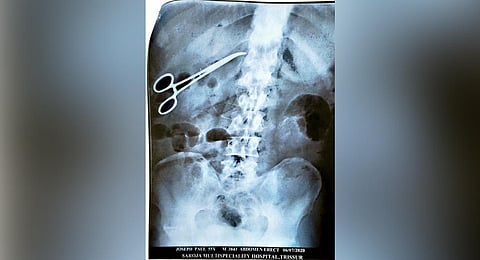

"The surgery was conducted on May 5. Later, the doctor said that there was presence of feces in the bile duct and hence another surgery was performed on May 12. My husband got discharged from hospital on May 30. After two weeks, when a CT scan was conducted on him, suddenly the junior doctor came and told us that there was infection in his intestine and another surgery should be performed. We got suspicious and shared it with other family members and friends. Before the surgery, we came back home and conducted an X-ray at another private hospital," said Bindu.

The X-ray revealed the presence of the forceps inside Joseph's body following which he was taken to Aswini Hospital where surgery was performed to remove the forceps on July 9.